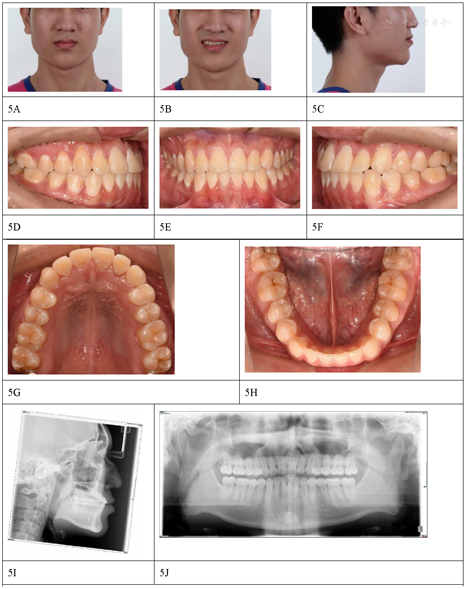

关系,上下牙列轻中度拥挤,磨牙关系为中性,右侧尖牙关系偏近中。全景片显示下颌第三磨牙阻生(图4)。2014年8月粘结全口直丝弓固定矫治器,上下颌前牙区配合邻面去釉获得间隙,逐步更换弓丝,上下颌采用0.019英寸×0.025英寸不锈钢丝作为稳定弓丝,配合颌间短Ⅲ类牵引维持前牙覆合覆盖及调整尖牙磨牙关系,保持3个月后拆除固定矫治器(图5),佩戴透明保持器。二次矫治治疗时长25个月(首次矫治结束后55个月),患者在二次治疗中已经拔除阻生的第三磨牙,侧切牙反

解除,拥挤解除,磨牙及尖牙关系均调整为中性。

二次矫治后随访至42个月,已停戴保持器1年,侧切牙反

及拥挤未复发,咬合稳定,牙列排齐(图7)。